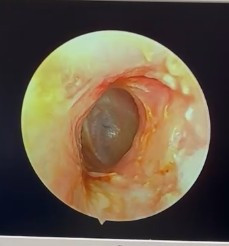

![]() |

| Ống tai sau phẫu thuật - Màng tai được nhìn thấy rõ dưới nội soi |